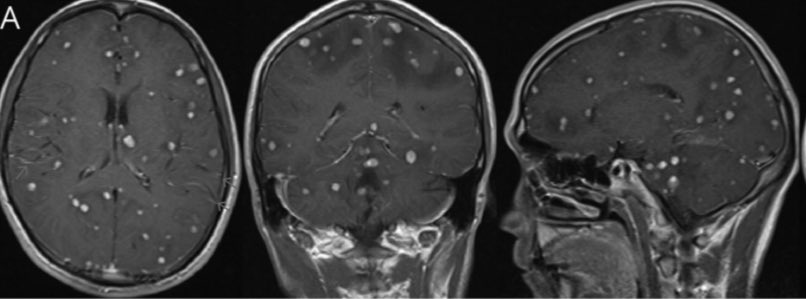

Patient is an avid international traveler. He presents with a bad headache.

It’s not cysticercosis